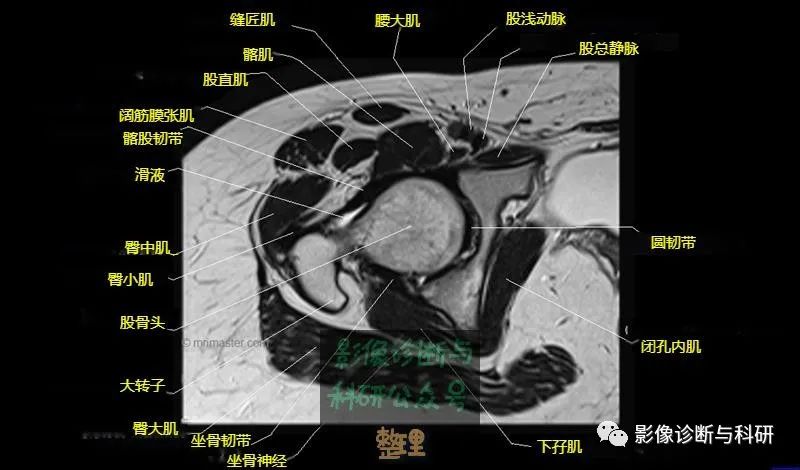

髋关节MR轴位详细标注